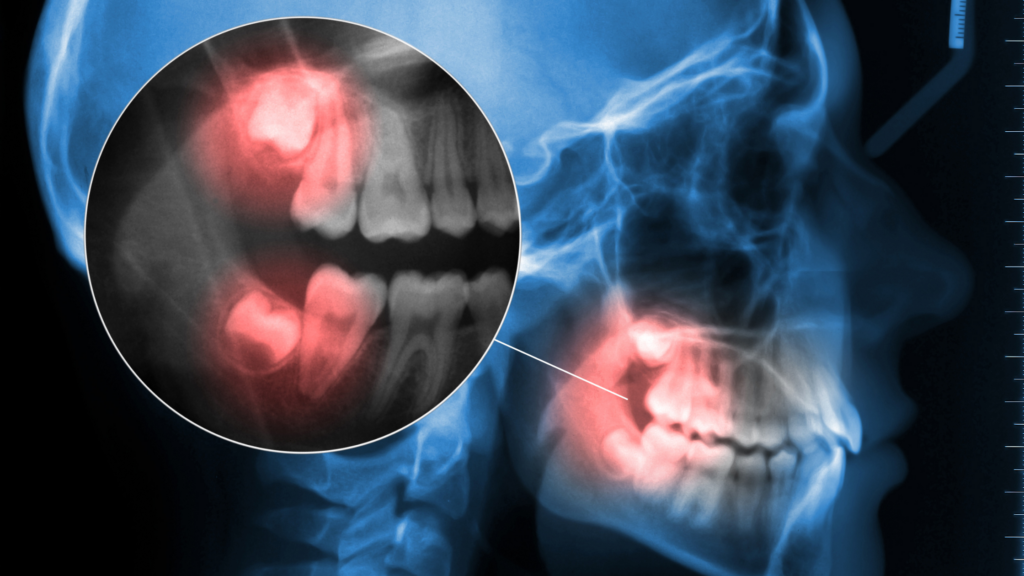

Wisdom Teeth Extractions and Nerve Damage

Concerned about nerve damage from wisdom teeth extractions? This expert guide from Dental Arts Toronto explains nerve proximity risks, how 3D imaging improves safety, and what to expect if nerve-related symptoms occur after your procedure.